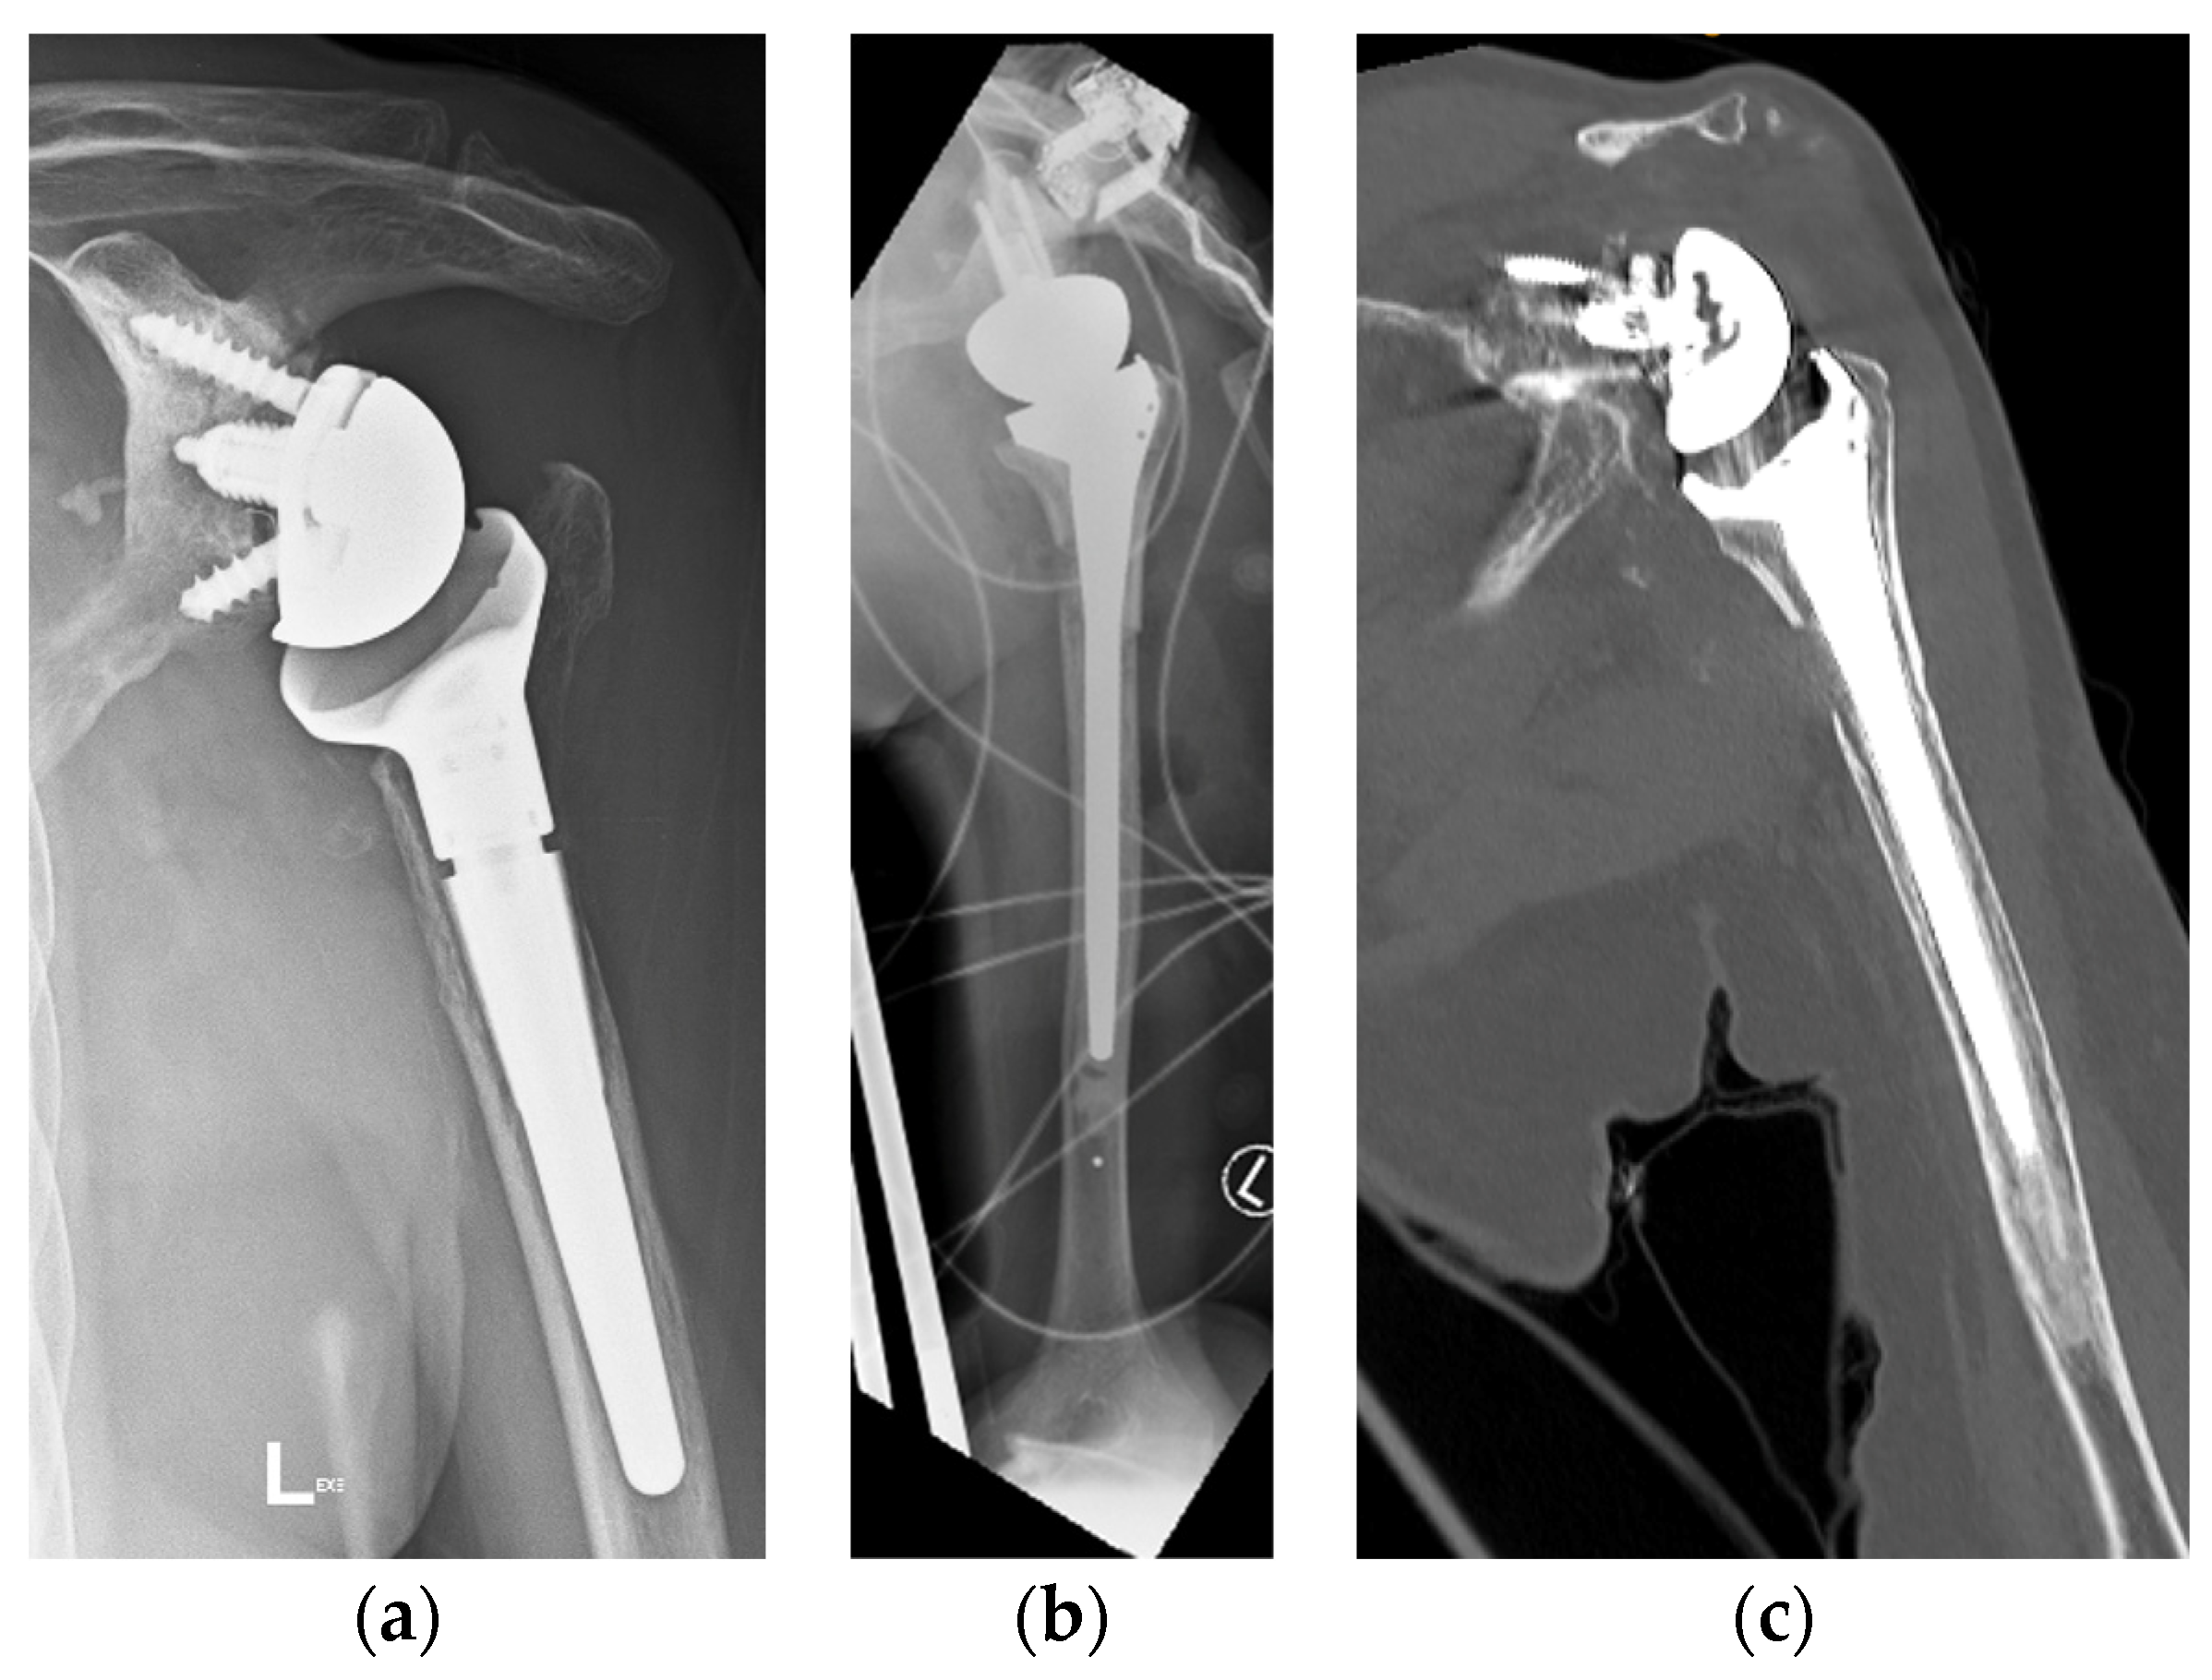

4.2. Radiologic Follow-Up

Two patients had repeat CT scans at two years, and one had X-ray at four years, showing complete graft union and no osteolysis (Figure 8). As mentioned, one patient was lost to follow-up, and another refused follow-up imaging.

Figure 8.

(a) Preoperative anteroposterior (AP) X-ray showing bone loss on the proximal humerus; (b) immediate postoperative AP X-ray showing reconstruction of the proximal humeral defect using an APC; (c) coronal CT scan showing union of the APC with the native humeral shaft.